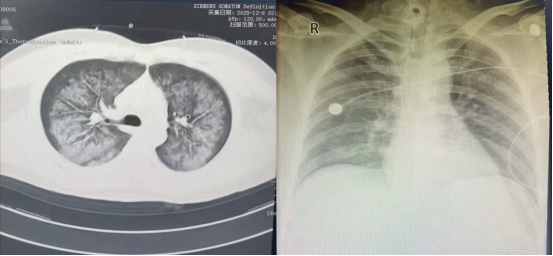

左图12月8日胸部CT,右图12月14日床旁胸片

当天14时前,遵医附院重症医学团队抵达该院ICU,即刻投入抢救。该30岁男性患者因“咳嗽、咳痰1月余,呼吸急促伴咯血12+小时”入院。1月前受凉后咳嗽咳痰,自服感冒药无效;12+小时前突发剧烈咳嗽、气促、鲜红色咯血及呕吐咖啡色胃内容物,家属于当日凌晨3时25分送至松桃县人民医院急诊科,经胸部CT诊断为“肺部感染”,收入重症医学科。

入院后予无创呼吸机辅助呼吸,患者气促未改善、血氧饱和度难以维持,病情快速进展。5时15分尝试床旁气管插管并行有创机械通气,因患者肥胖、颈短,会厌暴露极差(Cormack分级Ⅳ级),插管失败,5时30分紧急行气管切开术,术后予100%纯氧通气,仍无法改善呼吸氧合,循环需大剂量升压药维持。经抗休克、保护性通气等治疗后,患者病情无缓解,呼吸循环障碍进行性加重伴严重酸中毒,生命垂危,ECMO成为唯一救治希望。

当日20时,团队护送患者带机转运至遵医附院重症医学科。入科查体,T37.2℃,R20次/分,P123次/分,BP113/66mmHg(大剂量升压药维持),SPO₂96%;患者气管切开接转运呼吸机通气,呼之能应,双肺呼吸音粗、可闻湿性啰音。科室ECMO治疗护理小组立即接管患者,制定个性化综合诊疗方案。治疗期间密切监测血流动力学参数,动态追踪炎症指标及肝肾功能、凝血功能等,通过心脏彩超精准评估容量,予VV-ECMO、镇静镇痛联合呼吸支持,同步开展抗感染、抗休克、血液透析(兼顾容量管理与炎症清除)、脏器保护、营养支持等治疗。

经精准救治,患者病情逐步好转,肺部感染得到控制,于12月13日顺利撤机,后续继续气管切开呼吸机辅助通气。随着炎症指标下降,呼吸机参数逐步下调,患者自主呼吸恢复良好,12月17日拔除气切套管并封堵切口,配合康复团队完成阶梯式康复训练,12月19日顺利转回松桃县人民医院继续治疗。